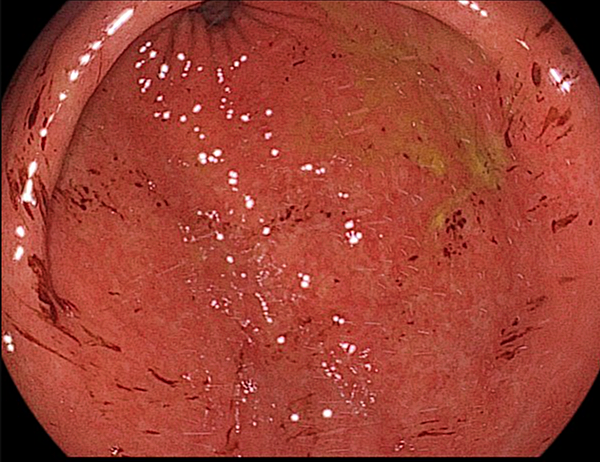

출혈성 위염

- 막에 출혈이 발생하여 붉은 반점이나 검붉은 색 변화가 나타나는 염증성 질환입니다.

- 헬리코박터 파일로리균 감염, 아스피린, 소염제 등의 약물 복용, 과도한 알코올 섭취, 흡연, 스트레스, 심한 화상, 외상, 쇼크 등 다양한 원인으로 인해 발생할 수 있습니다.

- 속 쓰림, 소화불량, 복통, 흑색 변, 혈변, 토혈 등의 증상이 나타날 수 있습니다. 심한 경우 빈혈이나 쇼크가 발생할 수도 있습니다.

- 원인에 따라 헬리코박터 파일로리 제균 치료, 지혈제, 위산 분비 억제제, 점막 보호제 등을 사용하여 치료합니다.

- 출혈성 위염은 위 점막의 손상 정도가 심하고, 출혈로 인해 빈혈이나 쇼크 등의 합병증이 발생할 수 있으므로 적극적인 치료와 관리가 필요합니다.